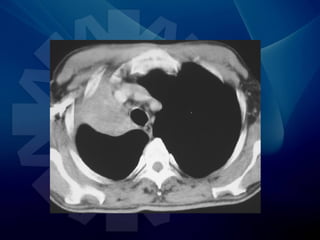

• TAC